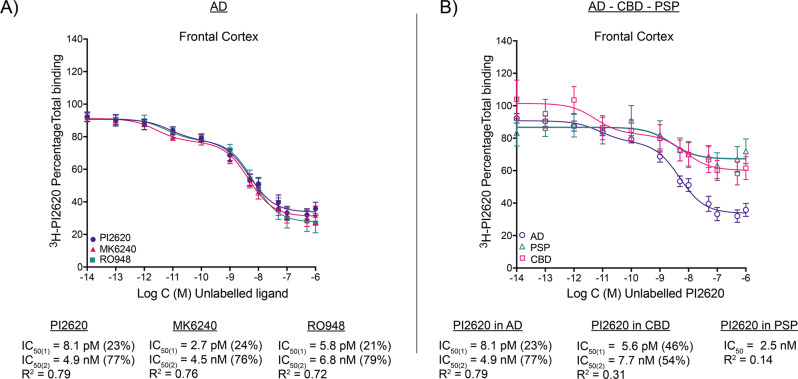

3H-PI2620 comparative competitive studies with unlabelled MK6240 and RO948 in AD brains

We further analysed the binding behaviour of 3H-PI2620 in AD brains by comparing its binding properties to those of MK6240 and RO948 in the same AD tissue. Competitive binding studies were carried out in the FC with 3H-PI2620, using increasing concentrations of unlabelled MK6240 or RO948 in the same tissue. The results are shown in Fig. 2A. MK6240 competed with 3H-PI2620 for two binding sites (IC50(1) = 2.7 pM; and IC50(2) = 4.5 nM) and RO948 competed with 3H-PI2620 for two binding sites (IC50(1) = 5.8 pM; and IC50(2) = 6.8 nM), compared with unlabelled PI2620 versus 3H-PI2620 (IC50(1) = 8.1 pM; and IC50(2) = 4.9 nM). Thus, unlabelled MK6240, RO948 and PI2620 demonstrated comparable binding affinities for two binding sites with similar proportions binding to the SHA (>20%) and HA (>70%) binding sites.

3H-PI2620 competitive binding studies in AD, CBD and PSP brain tissue

To further characterise the binding properties of 3H-PI2620 in PSP and CBD compared to AD FC brain tissue, competitive studies using increasing concentrations of unlabelled PI2620 versus 3H-PI2620 were carried out in CBD and PSP brain tissue. The results are shown in Fig. 2B. In CBD tissue, PI2620 competed in affinity for two binding sites (IC50(1) = 5.6 pM; and IC50(2) = 7.7 nM). These were in the same range as those reported above for AD tissue (IC50(1) = 8.1 pM; and IC50(2) = 4.9 nM). In PSP tissue, unlabelled PI2620 competed for only one binding site, in the nanomolar range (IC50 = 2.5 nM), which was comparable to the HA IC50(2) for CBD and AD in FC tissue. When the proportions of SHA and HA binding sites were calculated, AD FC tissue expressed 23 % SHA and 77 % HA, while CBD expressed 46% SHA and 54 % HA sites. For PSP only one HA site was detected.

3H-PI2620 saturation binding studies in the frontal cortex of AD brains demonstrated the presence of two binding sites and competition binding studies with unlabelled PI2620 versus 3H-PI2620 complemented the saturation data, demonstrating the presence of two binding sites (SHA and HA) in AD brains, with more than 70% corresponding to the HA site. These findings are in accordance with our earlier in silico data reports, suggesting that different tau tracers can detect multiple binding sites of AD tau fibril [ref. 28–ref. 31]. Moreover, tau spreads throughout the brain in the late stages of AD, with a high number of intraneuronal tau inclusions and extracellular ghost tangles made of 3 R and 4R isoforms in the cortical and hippocampal regions [ref. 43]. In addition, the severity of cognitive impairment in AD is reasonably well correlated with in vivo tau PET imaging [ref. 44, ref. 45] as well as Braak stages [ref. 46–ref. 48].

We also compared the binding properties of 3H-PI2620 with those of other 3R/4R tau tracers in the FC of AD brains, as in our earlier studies with MK6240 in the same AD patients’ brains [ref. 21]. Unlabelled RO948 competed for two binding sites with analogous affinities and, as before, our competitive studies between 3H-PI2620 and unlabelled MK6240 revealed two binding sites with affinities similar to those of unlabelled PI2620. Interestingly, in addition to the similar affinities for the three tau tracers in AD brains, the proportions of SHA and HA binding sites were also similar for the three tracers (the HA site accounted for more than 70% of the sites), stressing their similar binding behaviour in AD brains, rich in 3R and 4R isoforms. In our previous study, we showed that 3H-MK6240 had equivalent affinity (Kd = 0.3 nM) in the TC of AD brains [ref. 21]. Autoradiography of large frozen adjacent hemispherical brain sections from a sporadic AD case corroborated these results. 3H-PI2620, 3H-MK6240 and 3H-RO948 demonstrated the same binding pattern (visually/qualitatively) in the frontal and temporal lobes (neocortex) but a different binding pattern in the hippocampus and entorhinal cortex (allocortex). The three PET tracers all showed similar laminar patterns in the frontal and temporal lobes, with a higher binding intensity in the deeper cortical layers. Similar laminar distribution binding pattern was observed with the tau PET tracer THK5117 [ref. 35].

3H-PI2620 saturation binding studies in the FC of CBD brains demonstrated the presence of two binding sites, as in AD brains but only one site in PSP brains. The binding affinities of the binding sites in CBD and PSP brains were almost comparable to those in AD brains (Kd ranging from 0.1 to 1.2 nM). The main difference was in the Bmax (site density) values. The Bmax in CBD brain tissue was 2-fold lower than that in AD brain tissue whereas, in PSP, Bmax was almost 6-fold lower than in AD brain tissue. Thus, Bmax was 2.6-fold higher in CBD than in PSP brain tissue. These observations were confirmed by comparing the specific and NSP binding of 3H-PI2620 in these cases. In AD brain tissue, the specific binding was 2.5-fold and 6.5-fold higher than in CBD and PSP brain tissues, respectively.

Competitive studies with unlabelled PI2620 in CBD brain tissue also showed two binding sites, revealing a SHA site in the picomolar range that was not detectable in our saturation studies. In PSP, only one HA site was observed. Despite the differences in the binding affinity (for two binding sites) of PI2620 in CBD brain tissue, the proportions of the sites were equivalent. In silico studies on CBD tau fibrils predicted that, theoretically, among six potential binding sites, only two sites would be favourable for PI2620 (one entry site and one surface site) [ref. 31], while in AD tau fibrils where 12 binding sites would be available, PI2620 would preferentially bind to the core site and the entry site [ref. 28]. These findings clearly highlight the importance of the accessibility of tau-binding sites and fold conformational variability in these pathologies. In AD pathology, ghost tangles are present in heavily affected regions such as hippocampal CA1 and entorhinal cortex when the neurones have died but can hardly be visualised by AT8 staining since the epitopes of interest are washed out by proteases [ref. 49]. In this study we clearly observed in AD autoradiography that 3H-PI2620 binding differed between the different cortical areas, highlighting the possibility for this tracer to differentially bind to distinct tau formations.